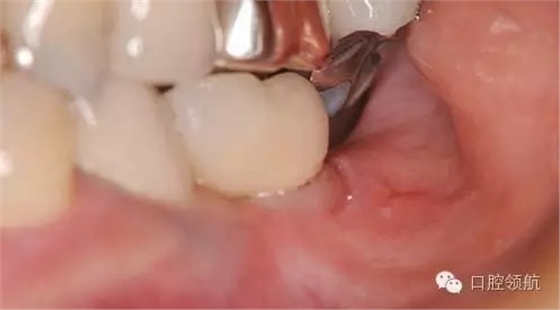

患者6年前接受的種植治療 ,由于主治醫(yī)的工作調(diào)動(dòng),由其他醫(yī)生繼續(xù)種植病人的牙周維護(hù)工作,初次問診時(shí)病人自訴刷牙時(shí)種植體周圍有不適感,診查時(shí)發(fā)現(xiàn)在種植體頰側(cè)的MGJ附近存在有小的潰瘍(圖1)。

圖1 種植體的頰側(cè)遠(yuǎn)中的軟組織上可見黃色的潰瘍。